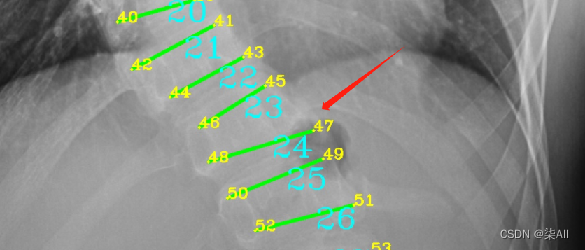

- 下图这个就不太行

下图这个就不太行